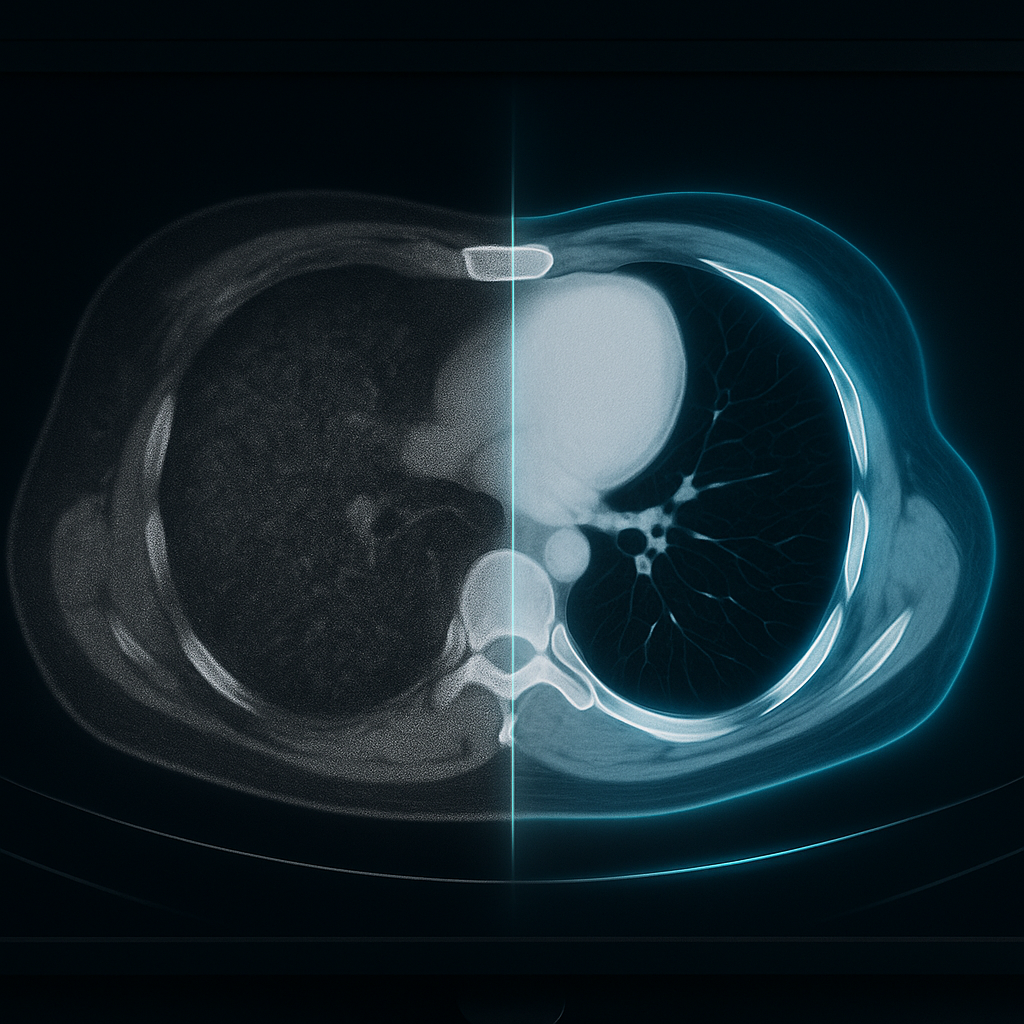

Radiology Reimagined: How AI Will Unlock New Capabilities for the Next Generation of Radiologists

Radiology is undergoing a transformation unlike anything we’ve witnessed in the last fifty years.

What started as simple X-ray interpretation has expanded into CT, MRI, PET-CT, high-resolution ultrasound, interventional radiology, and multimodal image fusion. Today, radiologists stand at the center of medicine — every department, from oncology to emergency medicine, depends on their insight.

And now, as Generative AI enters the scene, radiology is being reimagined yet again.

What AI Can Do Today — The Real, Practical Capabilities

Before diving into what AI may do in the future, let's focus on what it’s already doing right now, reliably, in real clinical settings.

1. Detect subtle abnormalities

AI models trained on millions of images can identify nuances that even experienced radiologists may overlook after long hours.

3. Auto-annotate and measure

AI can:

• star measure tumor sizes

• star segment organs

• star calculate volumes

• star mark regions of interest

• star track changes between previous scans

3. AI-Enhanced Imaging

AI can reconstruct high-quality

images from low-dose scans.

Impact:

• star icon Less radiation

• star icon Faster scans

• star icon Sharper clarity

• star icon Better diagnosis

• star icon Lower cost — a huge win for India